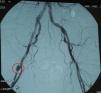

Con el diagnóstico de vasculitis séptica por SAMS se solicitó un ecocardiograma transesofágico que no evidenció vegetaciones ni datos sugestivos de endocarditis infecciosa, y una arteriografía que reveló la existencia de un pseudoaneurisma en la arteria femoral profunda derecha (fig. 4).